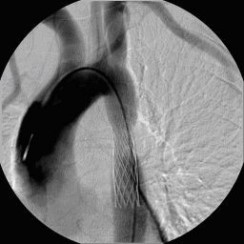

Aortenkoarktationsstenose vor Stentimplantation (Bild 1 von 4) Vorwärts »

« Zurück Aortenkoarktationsstenose nach Stentimplantation (Bild 2 von 4) Vorwärts »